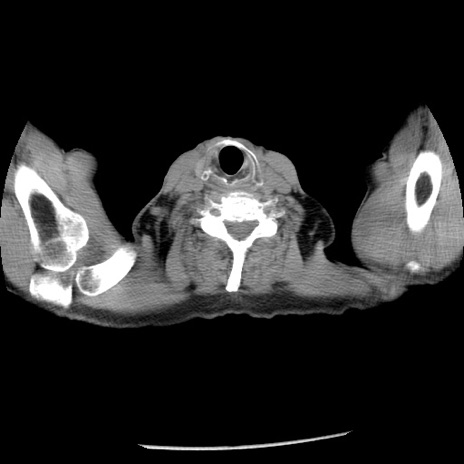

症例26(横断像)

【症例】80歳代男性

【主訴】嘔吐

【現病歴】昨晩2回嘔吐あり、今朝になっても嘔吐あり。来院。

【既往歴】胃潰瘍

【身体所見】意識清明、BT 37.6℃、BP 166/95mmHg、HR 100bpm、SpO2 97%、腹部:平坦・軟、腸蠕動音聴取良好、圧痛なし。

【データ】WBC 21900、CRP 1.46